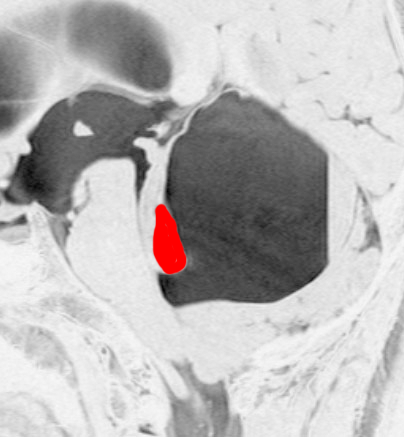

思春期の女の子にできた小脳腫瘍です。とても大きく見えますがほとんどが水たまり(のう胞といいます)。第4脳室が腫瘍で圧迫されて閉塞性水頭症になりました。のう胞の中に出血がありますが毛様細胞性星細胞腫では腫瘍内出血をしばしば見ます。右の写真で脳室が大きくなっています。こんなに大きいのに小脳症状は全くなくて,頭痛と嘔吐が症状でした。

赤で塗ったところだけが毛様細胞性星細胞腫です。これを取れば治ります。簡単な手術ですし後遺症も残りません。